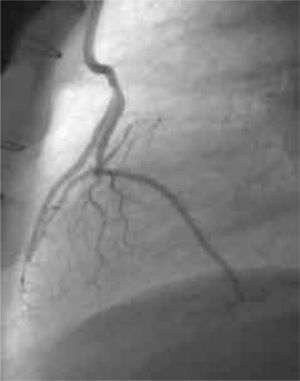

Permeabilidad de los injertosLos seis pacientes se evaluaron a 6 meses de la intervención mediante angiografías de control, constatándose la permeabilidad de todos los injertos realizados (Figs. 1 y 2).

El seguimiento fue clínico y angiográfico. A 6 meses del procedimiento se realizaron estudios angiográficos de control (Fig. 1) en todos los casos, constatándose en ellos la permeabilidad de todos los injertos realizados. A 15 meses (6–31) los pacientes intervenidos quirúrgicamente se encuentran asintomáticos, libres de eventos cardiovasculares, y no han requerido nuevos procedimientos de revascularización miocárdica quirúrgica ni percutánea.